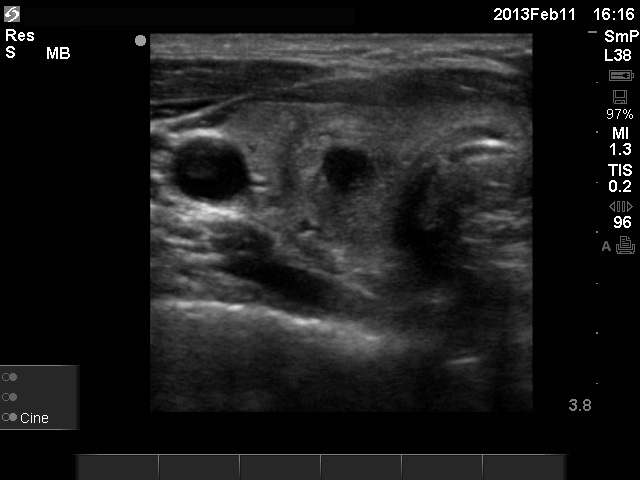

11 months after init. investig. |

7.30 |

0.18 |

4 months after delivery |

Nothing |

71 |

0.24 |

11.9 |

The relapse of de Quervain's thyroiditis in the contralateral lobe is a very frequent finding but not one year after the appearance of the disease. We supposed that the immunological changes during and after pregnancy explained the relatively late relapse of the disease.